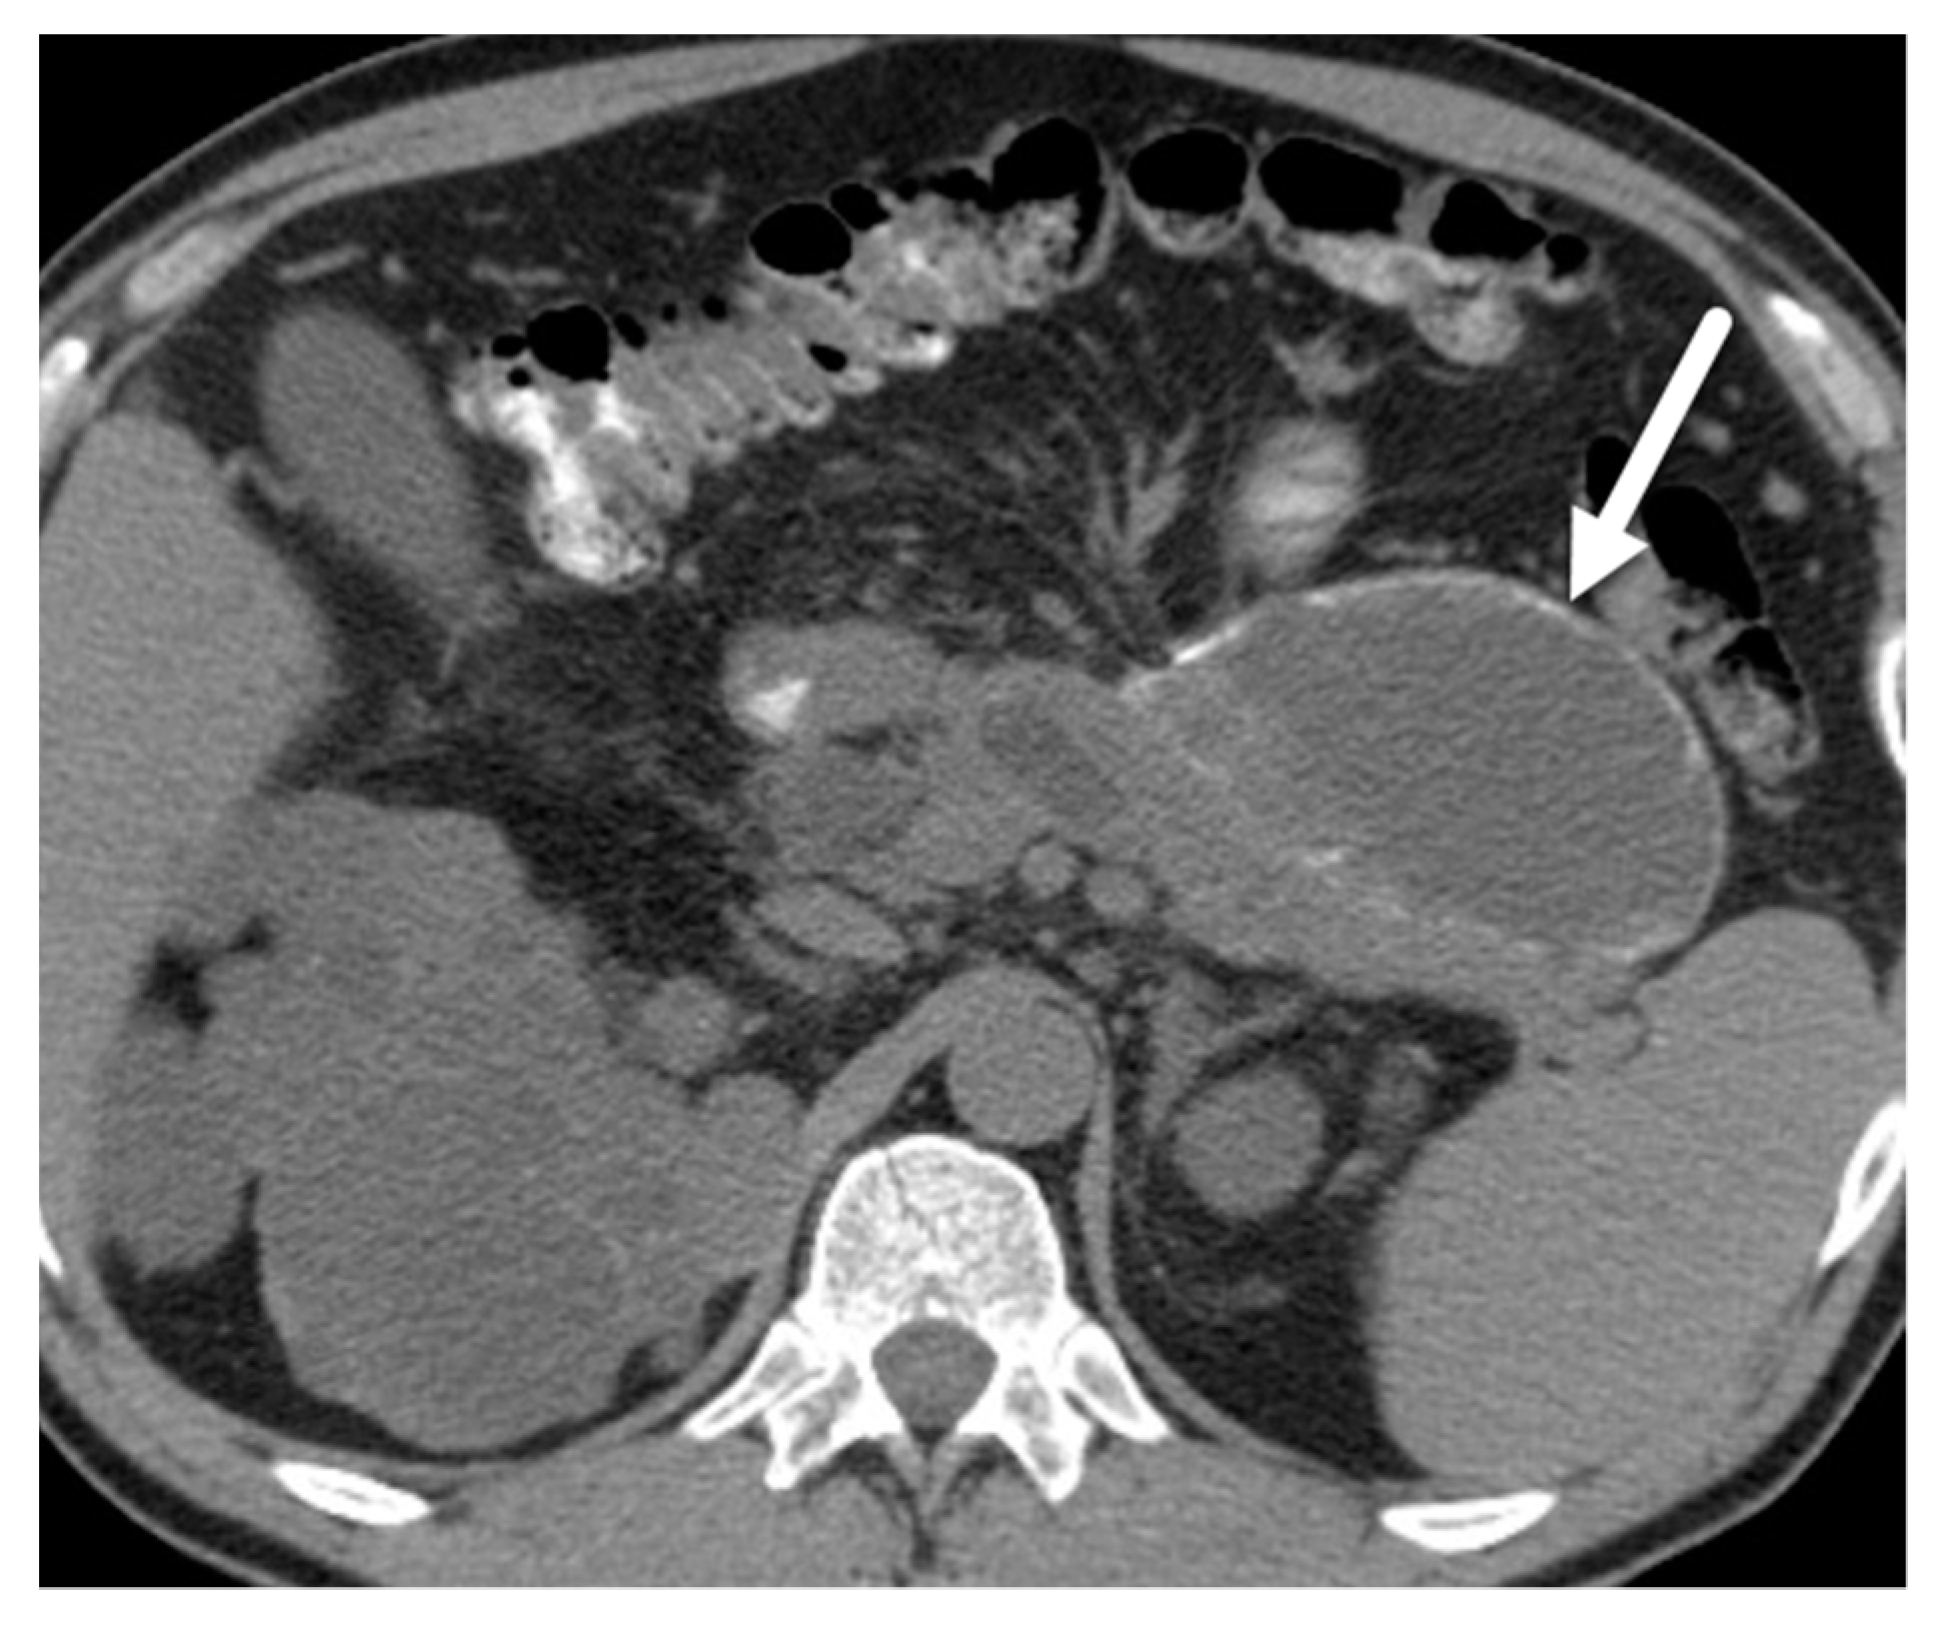

- Mamone, G.; Barresi, L.; Tropea, A.; Di Piazza, A.; Miraglia, R. MRI of mucinous pancreatic cystic lesions: A new updated morphological approach for the differential diagnosis. Updates Surg. 2020, 72, 617–637. [Google Scholar] [CrossRef] [PubMed]

- Tirkes, T.; Aisen, A.M.; Cramer, H.M.; Zyromski, N.J.; Sandrasegaran, K.; Akisik, F. Cystic neoplasms of the pancreas; findings on magnetic resonance imaging with pathological, surgical, and clinical correlation. Abdom. Imaging 2014, 39, 1088–1101. [Google Scholar] [CrossRef] [PubMed]